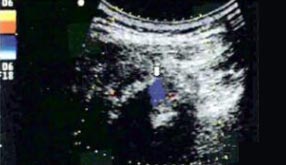

肌骨超声(musculoskeletal ultrasound,MSUS)技术是通过高频超声(3~17Hz)扫描提供优异的临床图像,以清晰显示肌肉等软组织层次关系及其内部机构来诊断肌肉骨骼系统疾病的新型超声检查技术。通过肌骨超声,医生可以分辨毫米级以下动态的这些组织结构肌肉、肌腱、韧带、关节囊、关节面及周围神经等浅表软的毗邻关系、形态大小、结构纹理、血流分布,从而获取这些组织器官的解剖变异、炎症、退行性病以及创伤等病变的全方位信息,从而对疾病进行精准评估。

动态观察滑膜血流信号,早期监测RA活动

清晰显示滑膜异常形态,定量评估RA炎性